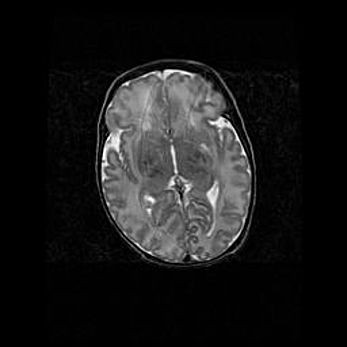

Множественные кисты обоих полушарий головного мозга, наибольшая из них в правой затылочной области. Ассиметричная атрофическая гидроцефалия.

Возраст: 7 месяцев

Вес: 5660 г

Пол: мужской

Окружность головы: 41,5 см

Срок гестации: 28-29 недель

Кисты головного мозга развиваются в результате многоочаговых некрозов вещества мозга и возникают вследствие перенесенной перинатальной инфекции, менингитов, энцефалитов, асфиксии, родовой травмы, расстройств мозгового кровообращения различного генеза. Образованию кист в веществе головного мозга плодов и новорожденных способствуют такие факторы, как высокое содержание в нем воды, недостаточная (или отсутствие) миелинизация и слабая астроглиальная реакция на повреждение.

Кисты могут сочетаться с гидроцефалией и другими поражениями головного мозга.